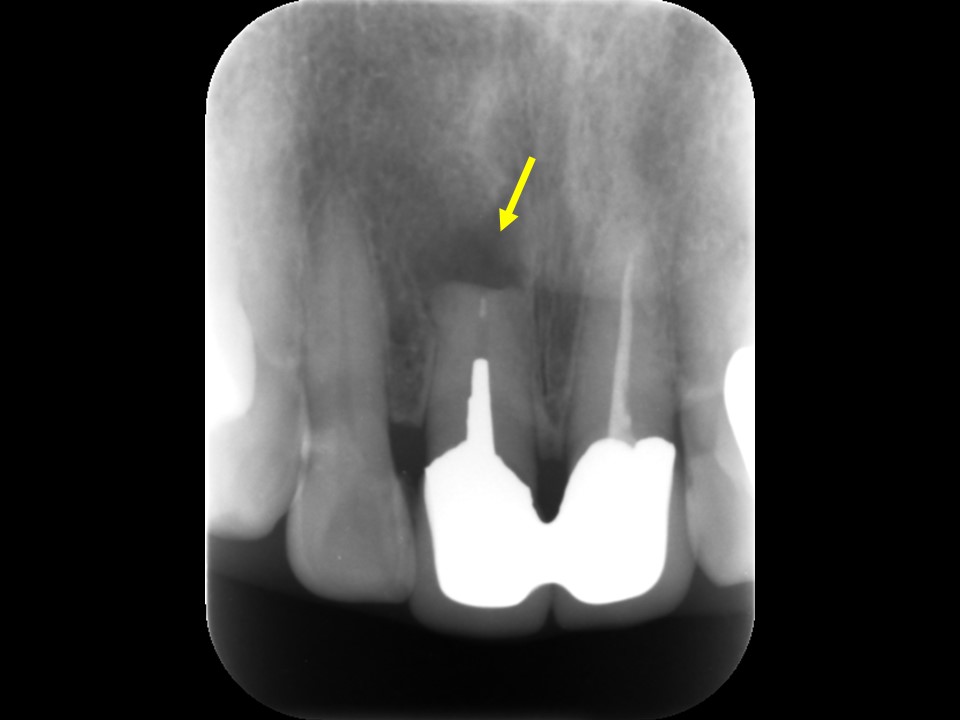

歯根端切除・逆根管充填6か月後レントゲンおよびCT画像です。

根尖部の黒いX線透過像は完全に消失しており、歯槽骨が再生し根尖病変の治癒を認めます。